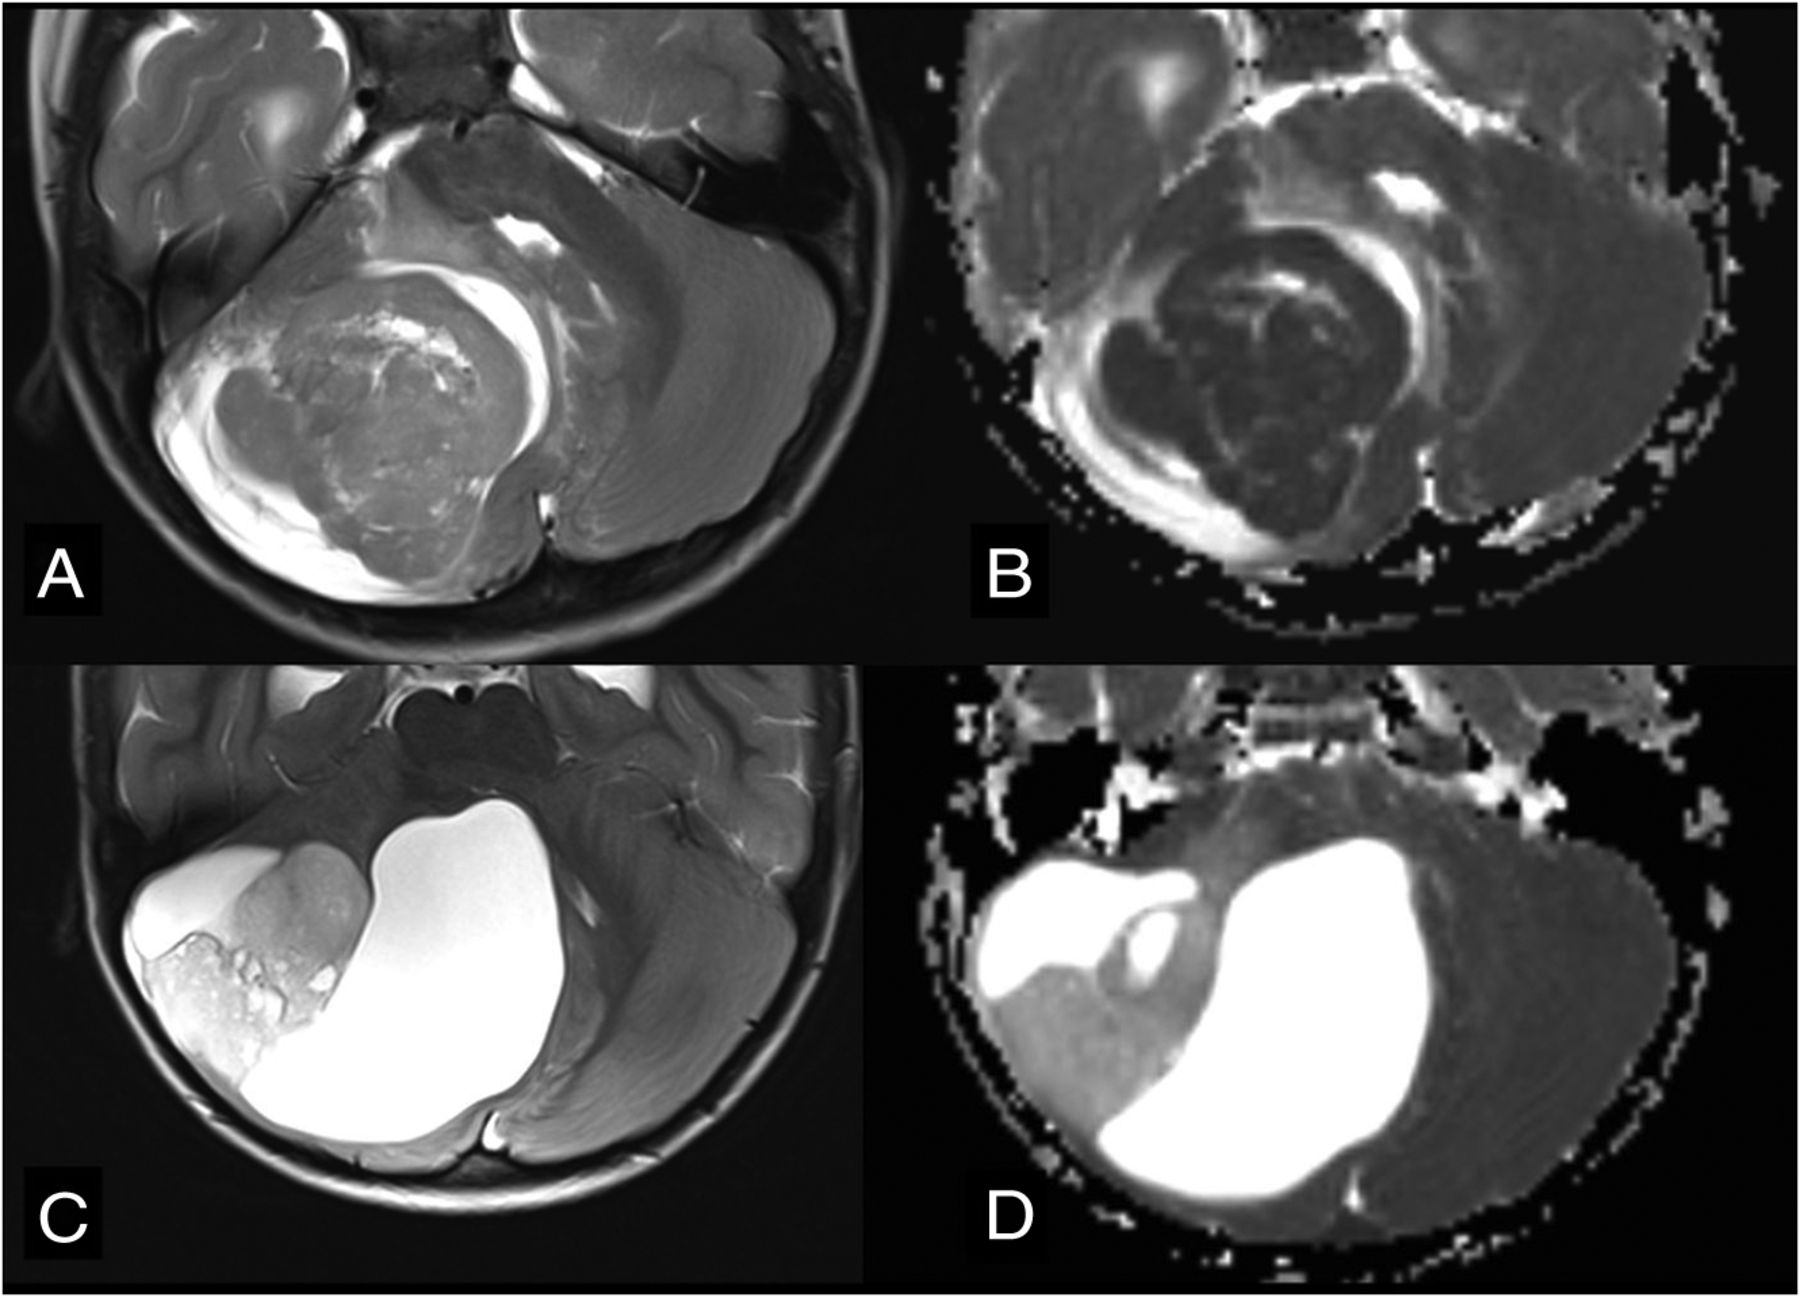

Differential diagnoses in cases of posterior fossa tumors originating from the cerebellar hemisphere. Axial T2WI (A) and axial ADC map (B) show SHH medulloblastoma (flow chart 2, number 111) in a typical peripheral location within the cerebellar hemisphere due to its origin from ganglionic cell precursors. Note very low ADC values (ie, diffusion restriction). Axial T2WI (C) and axial ADC map (D) show the typical appearance of a pilocytic astrocytoma (flow chart 2, number 123) originating from the cerebellar hemisphere. Note the typical nodule and appearance of cysts and much higher ADC values in comparison with the medulloblastoma.